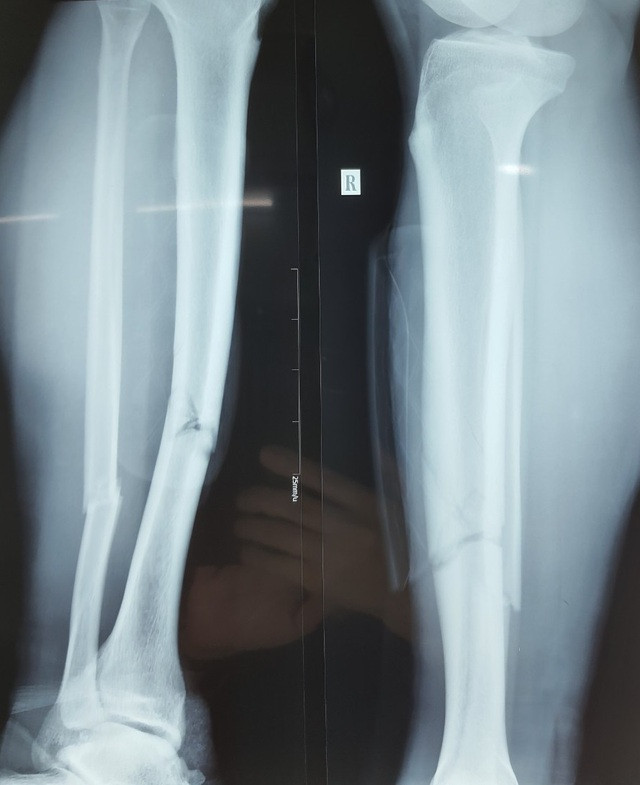

Ngay khi tiếp nhận bệnh nhân, các bác sĩ đã tiến hành hội chẩn chuyên khoa, chăm sóc giảm đau và thực hiện chụp X-quang để đánh giá tình trạng chấn thương. Qua thăm khám cho thấy chỉ số máu và tim mạch của bệnh nhân đều ổn định, bình thường, kết quả X-quang ghi nhận, chân phải của Đỗ Hùng Dũng bị gãy xương mác và xương chày ở 1/3 giữa dưới cẳng chân.

Các bác sĩ nhận định tình trạng chấn thương của Hùng Dũng khá nghiêm trọng, cả 2 xương đều bị gãy. Tuy nhiên, điều may mắn là vị trí gãy ít di lệch, không bị dập nát hoặc vỡ xương phức tạp. Qua hội chẩn, các bác sĩ quyết định mổ hở để kết hợp xương cho Hùng Dũng.

Hình ảnh X-quang cho thấy xương của Hùng Dũng bị gãy- ảnh Vân Sơn Ca phẫu thuật được bắt đầu lúc 9h sáng nay. Sau khi rạch da, tiếp cận vị trí bị gãy xương, các bác sĩ sẽ sử dụng đinh và nẹp để cố định vị trí bị gãy. Ca phẫu thuật được các bác sĩ giỏi về chuyên khoa y học thể thao thực hiện, các bác sĩ đánh giá là không quá phức tạp.